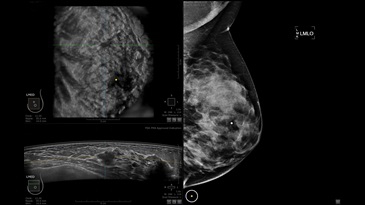

GE INVENIA ABUS – это современный УЗИ аппарат, который создан для точной и эффективной диагностики сканирования с высокой плотностью молочных желез. Выявляемость патологий раковых и предраковых стадий заболевания составляет 55%, что в конечном счете позволяет ставить врачу точные и своевременные диагнозы. Традиционные методы использования маммографии не показывают такой выявляемости, ограничиваясь лишь 3-38%.

УЗИ-аппарат GE INVENIA ABUS позволяет проводить максимально операторонезависимые процедуры, что значительно снижает риск неправильной постановки диагноза и сопутствующие издержки на обработку информации. Система готовит отчет в течение 3-х минут после сканирования, это безусловное преимущество по сравнению с обычным УЗИ сканером.

• Получение объемных 3D изображений с возможностью покадрового просмотра

• Отображение объемных 3D ультразвуковых изображений, которые состоят из традиционных поперечных и воссозданных коронарных и сагиттальных проекций

• Стандартизованная ориентация изображения: «толстый срез» в коронарной плоскости; поперечная; сагиттальная плоскость; радиальный и антирадиальный поворот изображения; просмотр исключительно области интереса

• Одновременный просмотр двух изображений для сопоставления в коронарной плоскости